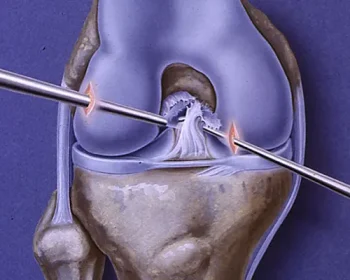

ACL and PCL arthroscopic reconstruction is a minimally invasive surgery to repair torn ligaments in the knee, promoting faster recovery and improved stability.